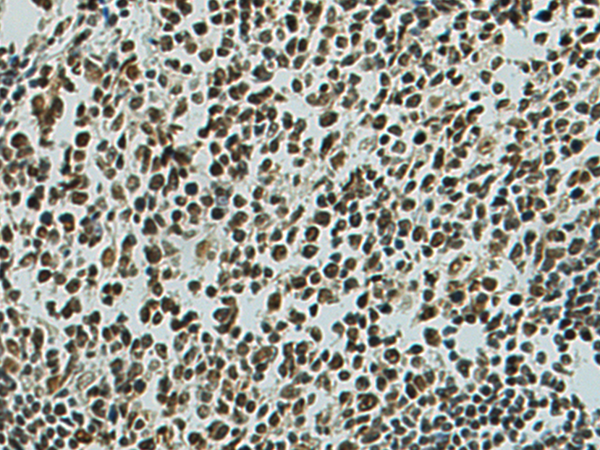

分类: 科研抗体货号: P02882别名: LMP10; MECL1; beta2i应用: WB,IHC反应种属: Human, Mouse, Rat